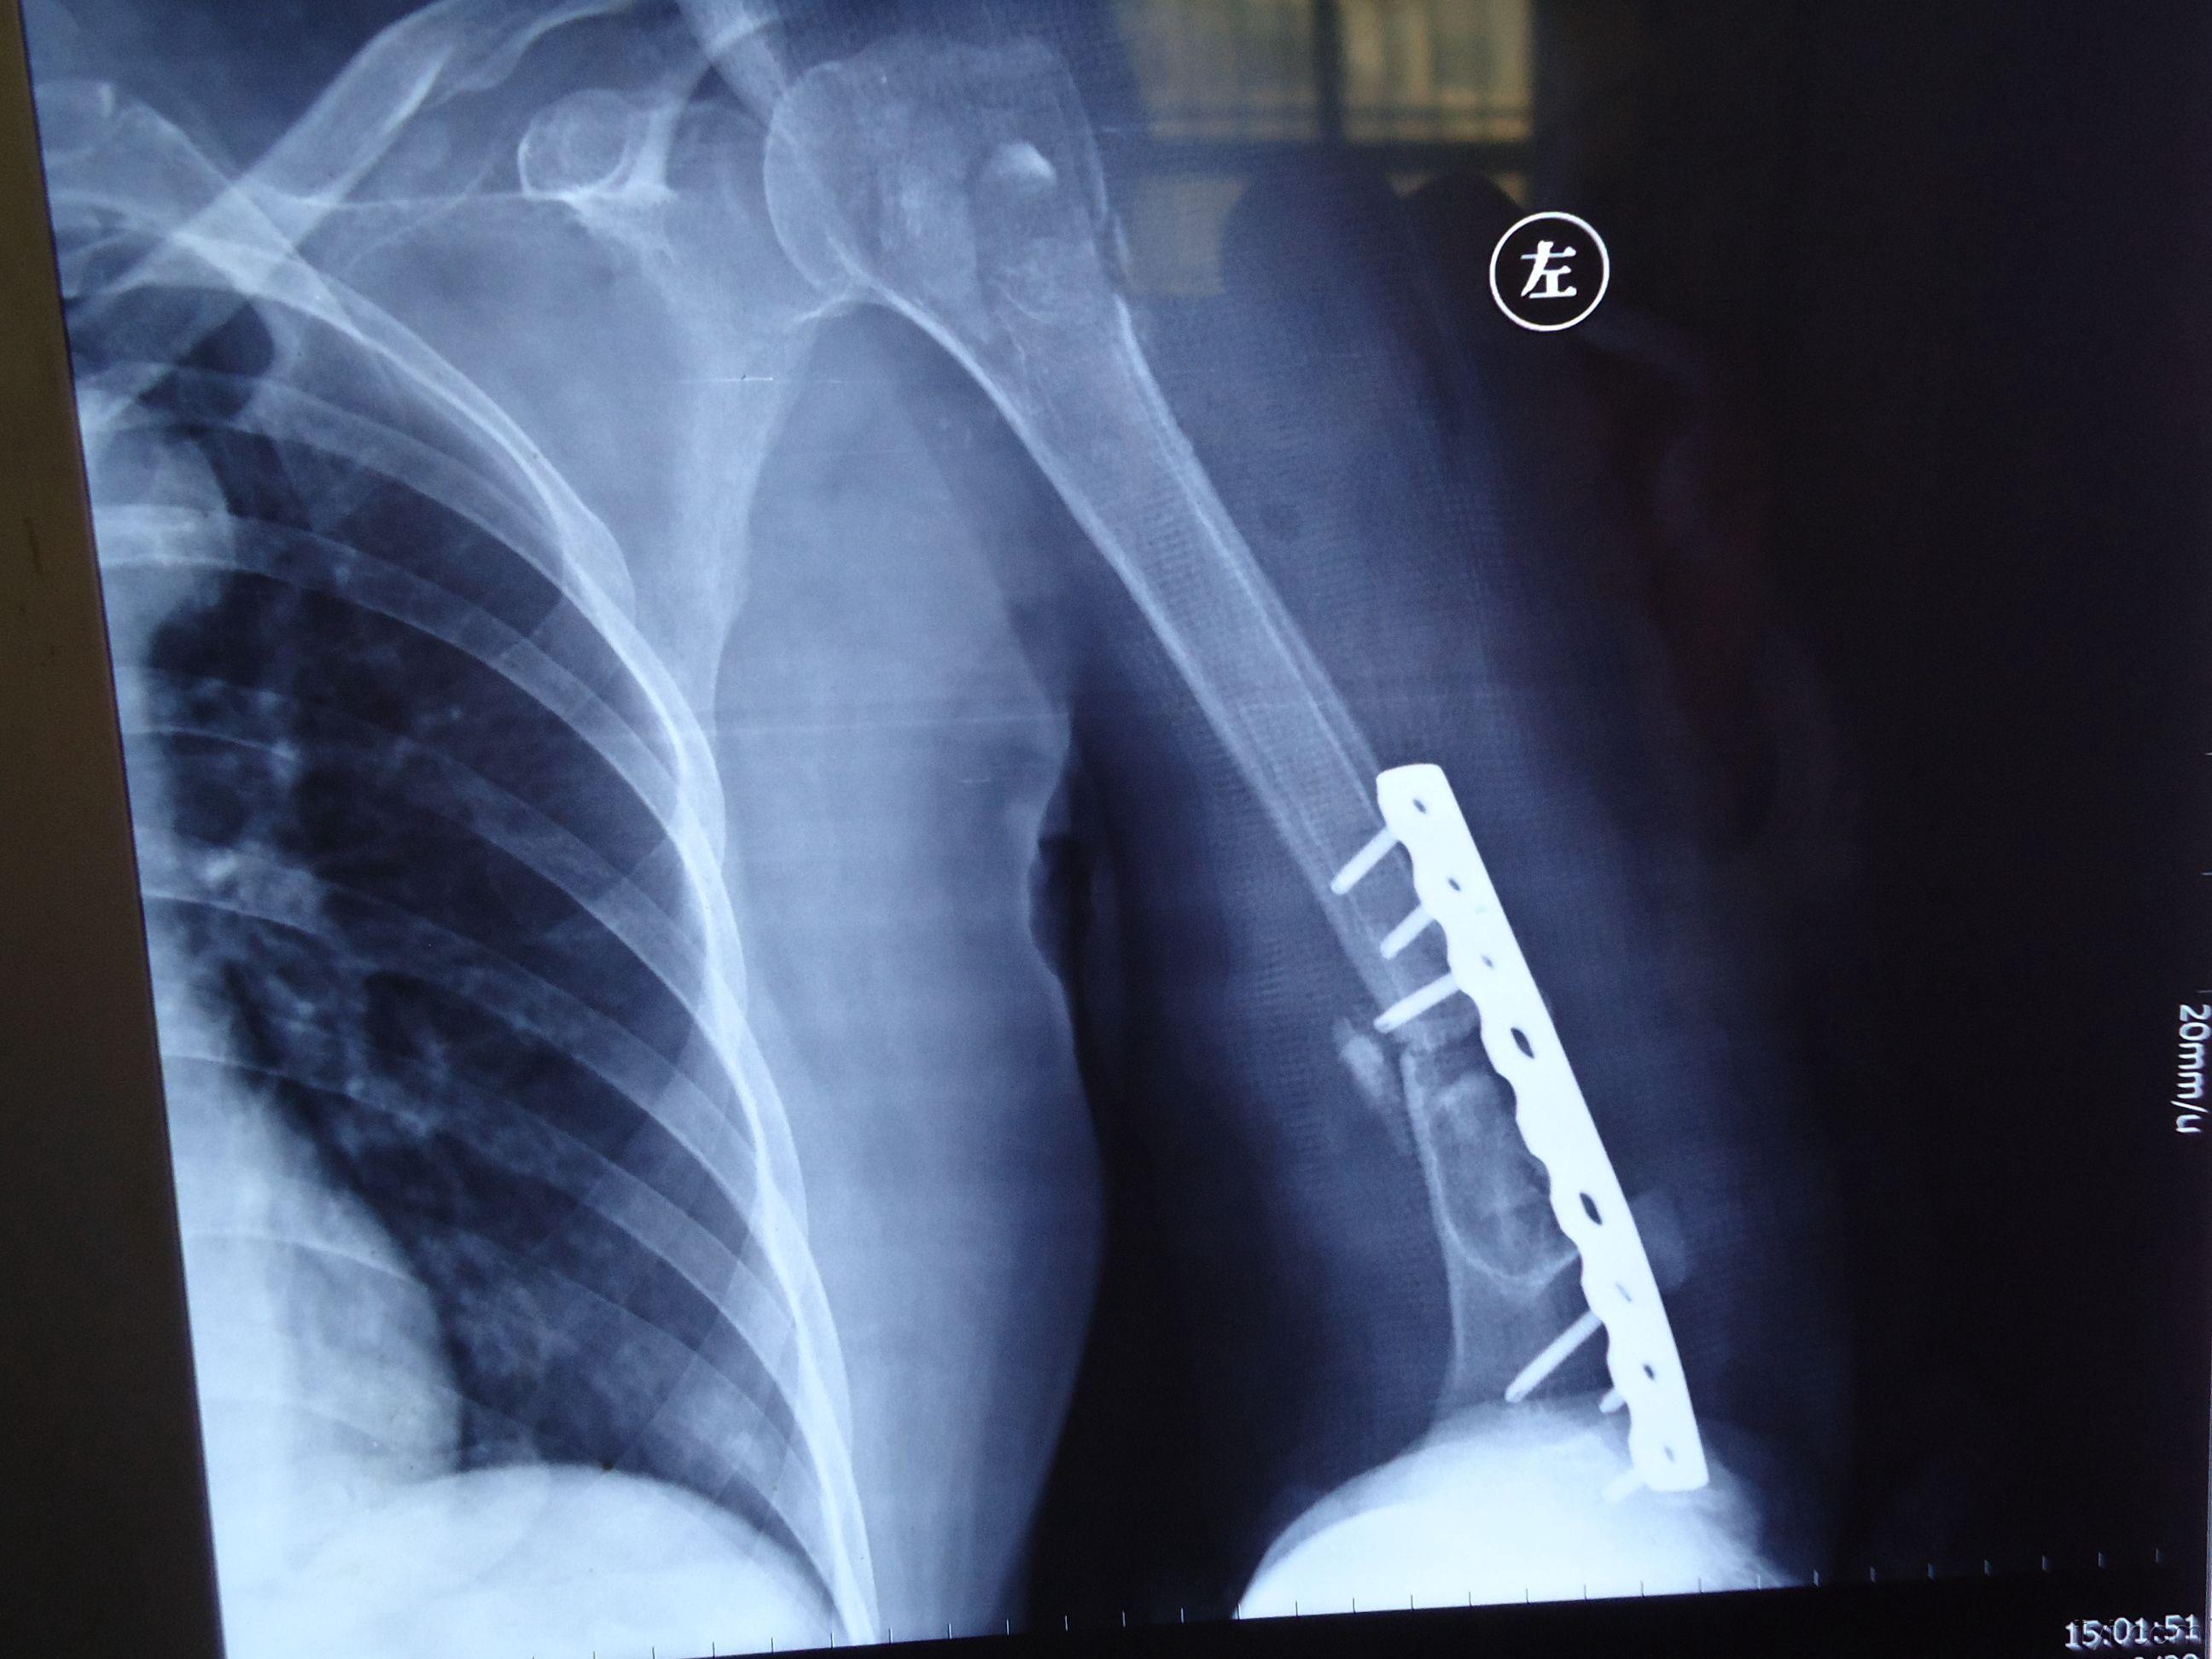

植骨 钢板内固定术后

肱骨干简单骨折一期行双钢板内固定 植骨术